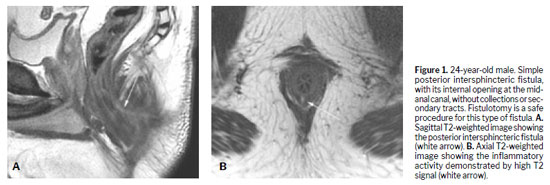

Various techniques can be used for the morphological evaluation of the fistula and its relationships with pelvic and perianal structures, including X-ray fistulography, computed tomography, endorectal or transrectal ultrasound, and MRI(11). Surgeons have access to 3D reconstructed endorectal ultrasound as a tool that can be used in the office and in outpatient settings, making it helpful in characterizing fistulas and anorectal abscesses, identifying the internal opening, and determining the main tract of a fistula. Among the various imaging modalities, MRI is the method of choice for studying anorectal fistulas, because it is superior for characterizing secondary tracts(2,6). Evidence from observational studies summarized in a narrative review has shown that MRI-guided surgery can reduce the likelihood of recurrence by approximately 75%, mainly by allowing precise preoperative identification of fistulous tracts and secondary extensions that might otherwise go undetected(5). Prospective observational studies suggest that this imaging method, used preoperatively, modifies surgical strategy in approximately 10% of patients with primary fistulas and 21% of those with primary, secondary, or Crohn’s disease-related fistulas(1). The benefits are even greater for sphincter-preserving procedures(5). Certain aspects of fistula morphology favor certain surgical procedures, whereas other procedures are contraindicated by specific morphological characteristics(7). Several studies have discussed which are the most relevant characteristics to be described in MRI reports in the evaluation of anorectal fistulas, as well as the best form of presentation, such as structured reporting, to improve understanding on the part of the attending physician(2,5,12). However, in cases of complex anorectal fistulas, reports can still be challenging to interpret for adequate surgical planning(3). In recent years, 3D modeling has gained space as a promising tool to aid in surgical planning(3). Figures 1–5 demonstrate MRI-based strategies in the evaluation of perianal fistulas, highlighting traditional 2D sequences as well as 3D reconstructions.

(6): simple fistulas, for which fistulotomy is a safe procedure with high cure rates and no postoperative continence problems; and complex fistulas, in which there is significant involvement of the anal sphincter, associated with higher rates of recurrence and risk of incontinence, which should be treated exclusively with sphincter-preserving techniques.

(6).Among the possible surgical treatments, fistulotomy is the procedure most frequently performed for simple fistulas, which account for approximately 30–50% of cases, with a cure rate of approximately 95% when all tracts are treated. In general, fistulotomy results in a reliable cure and reasonable patient satisfaction when 2 cm of the most cephalic EAS is preserved, and it is generally used in intersphincteric and low transsphincteric fistulas

(1,6). However, fistulotomy carries a high risk of fecal incontinence, especially when performed for complex fistulas